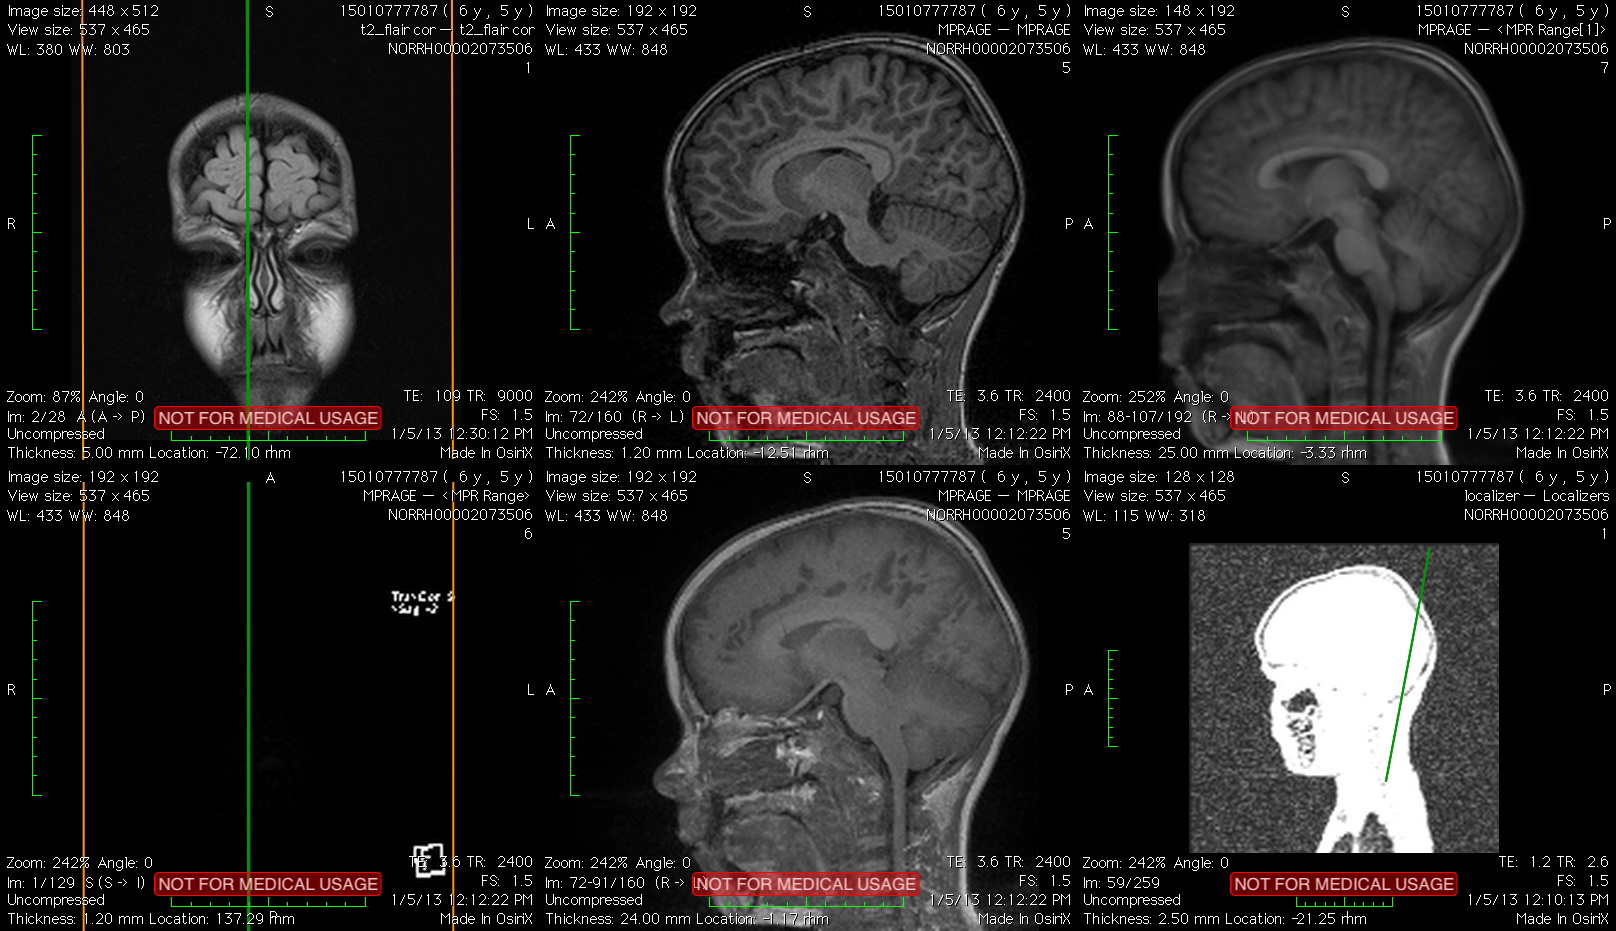

One of the presented artwork is Brain. Brain is a series of video products derived from personal artistic research on modern scientific discoveries and technological developments. Haraldur have MRI images of my son's brain and with the help of scientific software that can focus on the thickness of the pulp, I have come across an endless (seemingly) opportunity for representations on this remarkable body. I have started a dialogue with researchers from the Norwegian University and have received positive feedback on possible collaboration. The project has, over time, been supported by Visual Artists' Remuneration Fund, Gallery of Iceland and Atopia Center for Video Art and Experimental Film.

The fascination with the (almost) infinite possibilities of this detecting/imaging – the perfection in capturing the smallest of fibres, their thickness, length and shape – led Haraldur to dialogue and collaborate with scientists at the Norwegian University to develop the potential of his art practice. The artist has moved the still images through digital technologies into an audiovisual work in which the exact scientific data, on the one hand very concrete and real, appear at the same time as completely abstract, resembling the living structure of the microcosm. The video consists layers of images and detailed structures in which we penetrate deep into the bowels of the body, specifically the head, the place that controls our physical body, but also houses the mind and the whole elusive realm of thought and imagination. While MRI scans can capture the finest nuances and shades of physical matter, fibers and tissue, they cannot reveal anything about our minds. Haraldur's videos lead us here, into a space of imagination and unexpected poetics; they are a kind of authorial interpretation of the contemporary scientific method. They show that the world around us is best understood neither through the exact scientific method nor through subjective individual imagination, but precisely in the combination of these two seemingly contradictory approaches.